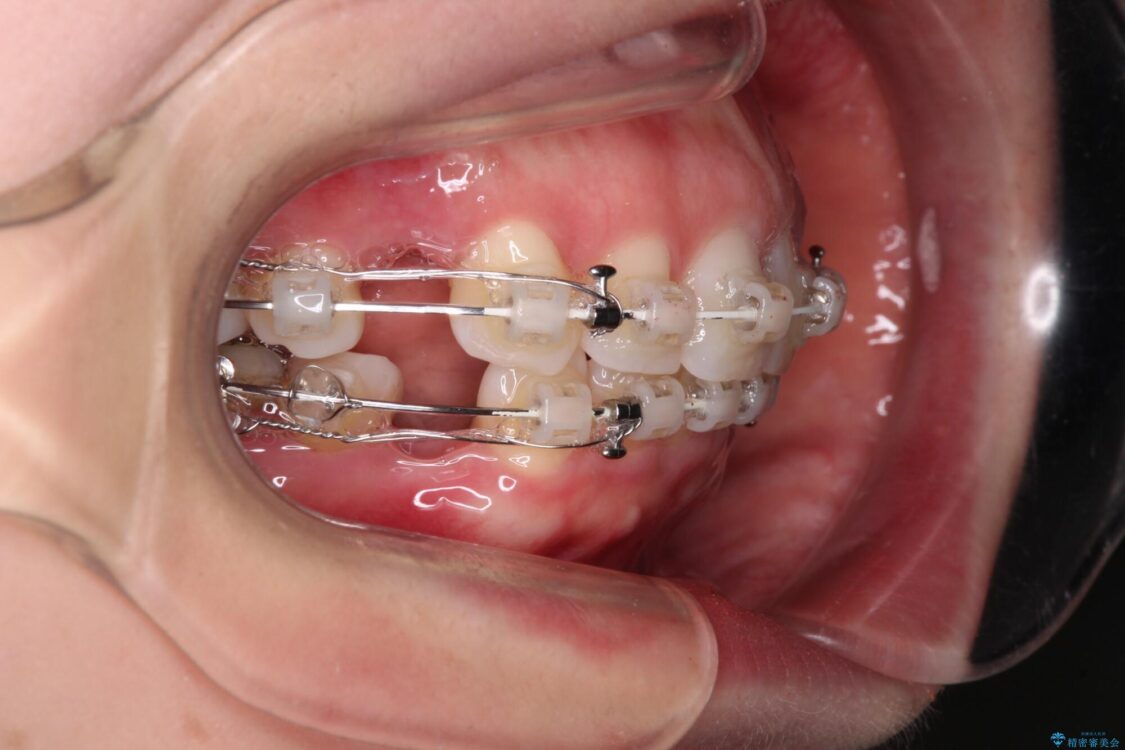

左下の大臼歯2本が顕著に舌側に傾斜しているため、まずは奥歯の咬み合わせを改善をし、その後上下左右の第1小臼歯4本を抜歯することで口元を引っ込めながら整えることとしました。

治療途中

• 【モニター】出っ歯と咬み合わせを改善 ワイヤー装置の抜歯矯正 治療途中画像